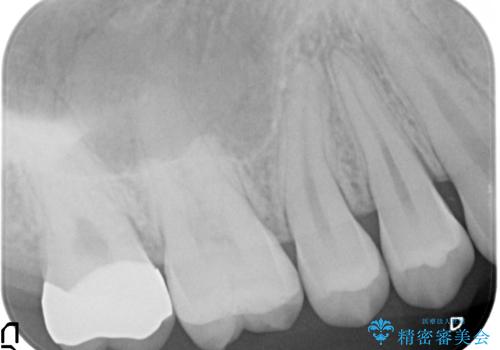

- 奥歯が虫歯になり、位置的に詰め物は難しかったため、被せものにする治療を行いました。

- 11万円 ジルコニアクラウンスタンダード10万円、仮歯1万円費用は治療当時の料金となります

頬側に咬頭が一つ多い歯であったのと、歯肉に近い位置が虫歯になっていたため、被せものでしっかり覆う治療を行いました。